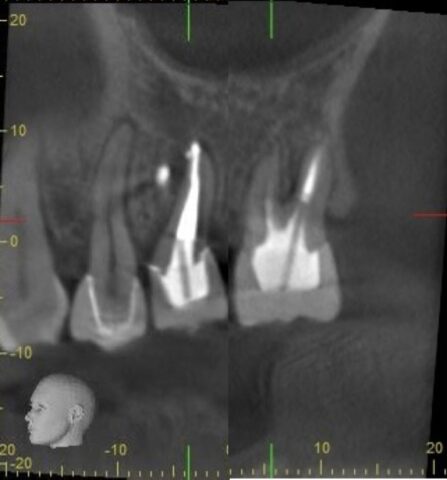

治療後6ヶ月のデンタル、CTです。

根っこの先で溶けていた骨もここまで回復しました!